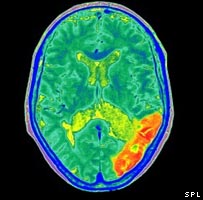

Imagem de cérebro com alzheimer

A doença degenerativa atinge principalmente idosos